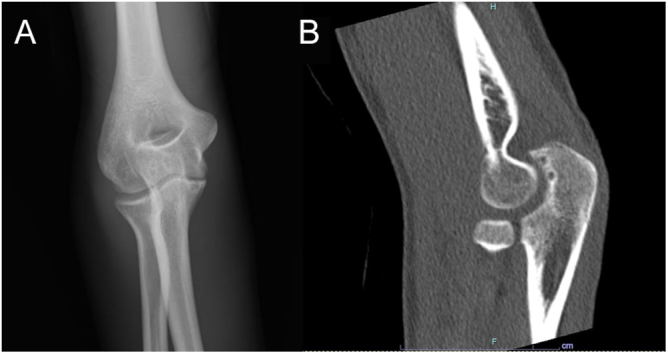

Summary: Hypophosphatasia (HPP) is a genetic disorder due to pathological variants in ALPL, the gene encoding tissue-nonspecific alkaline phosphatase (ALP). HPP is typically associated with bone-related symptoms, such as bone deformity, fractures and bone pain in children, but can appear in adults with symptoms resembling arthritis. A 22-year-old male experienced repeated and severe sudden attacks of joint pain in the elbows and knees. Magnetic resonance imaging and joint ultrasonography showed joint effusions indicating chronic inflammation. Blood biochemical tests revealed a remarkably low serum ALP level, and repeated examination confirmed a sustained low ALP level; urine phosphoethanolamine, plasma inorganic pyrophosphate and plasma pyridoxal-5'-phosphate levels were elevated, raising concern for HPP. While the patient had no history of premature loss of primary teeth, fragility fractures, muscle weakness or abnormalities in growth, genetic testing revealed a likely pathogenic and a pathogenic heterozygous variant in the ALPL gene, i.e., c.979T>C (p.Phe327Leu) and c.1559del (p.Leu520Argfs), confirming HPP. Additional genetic testing of his parents showed a heterozygous c.1559del variant in his father and a heterozygous c.979T>C variant in his mother. A diagnosis of adult HPP due to compound heterozygous mutations was therefore confirmed. Enzyme replacement therapy with asfotase alfa was then introduced; no attacks of arthralgia occurred in the 1-year period since then. This case highlights the possibility of HPP in adults who present clinically with repeated joint symptoms and low serum ALP levels but without bone-related symptoms.